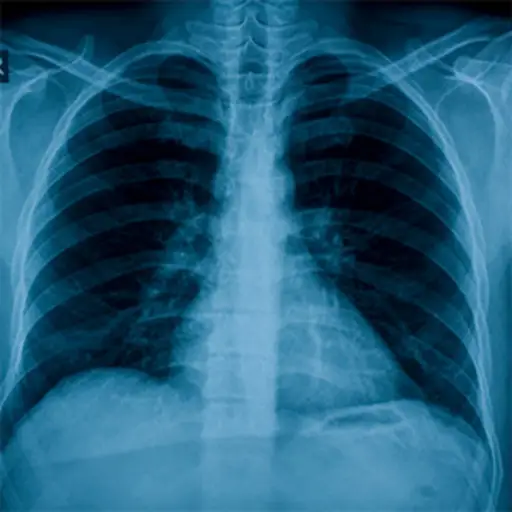

肺素

肺活量计测量气流以及肺部工作程度。当您呼吸到该设备时,它测量您呼吸的空气量,以及您能够吸气和呼气的速度。肺活量计可用于跟踪肺部随着时间的推移以及挑选疾病的恶化和进展的方式。